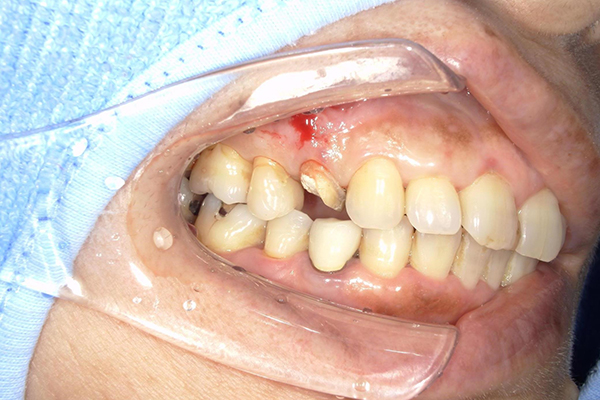

根管治療の終了直後

歯の色が気になるとのことで来院。検査してみると歯の神経にまで虫歯が達していたため、感染した歯髄を除去するため根管治療を行いました。

本ケースでは、レジンと呼ばれる歯科用プラスチックを用いたコアを採用しています。

レジンコアを立てて、被せ物ができるように補強します。

レジンコアを立てた後は、写真の通り細く削り形を整えます。